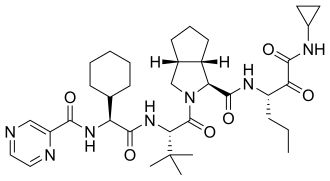

Passerini reaction has been employed for the formation of structures like α-amino acids, α-hydroxy-β-amino acids, α-ketoamides, β-ketoamides, α-hydroxyketones and α-aminoxyamides.[12] The Passerini reaction has synthesized α-Acyloxy carboxamides that have demonstrated activity as anti-cancer medications along with functionalized [C60]-fullerenes used in medicinal and plant chemistry.[12][25] This reaction has also been used as a synthetic step in the total synthesis of commercially available pharmaceuticals such as telaprevir (VX-950), an antiviral sold by Vertex Pharmaceuticals and Johnson & Johnson.[12]